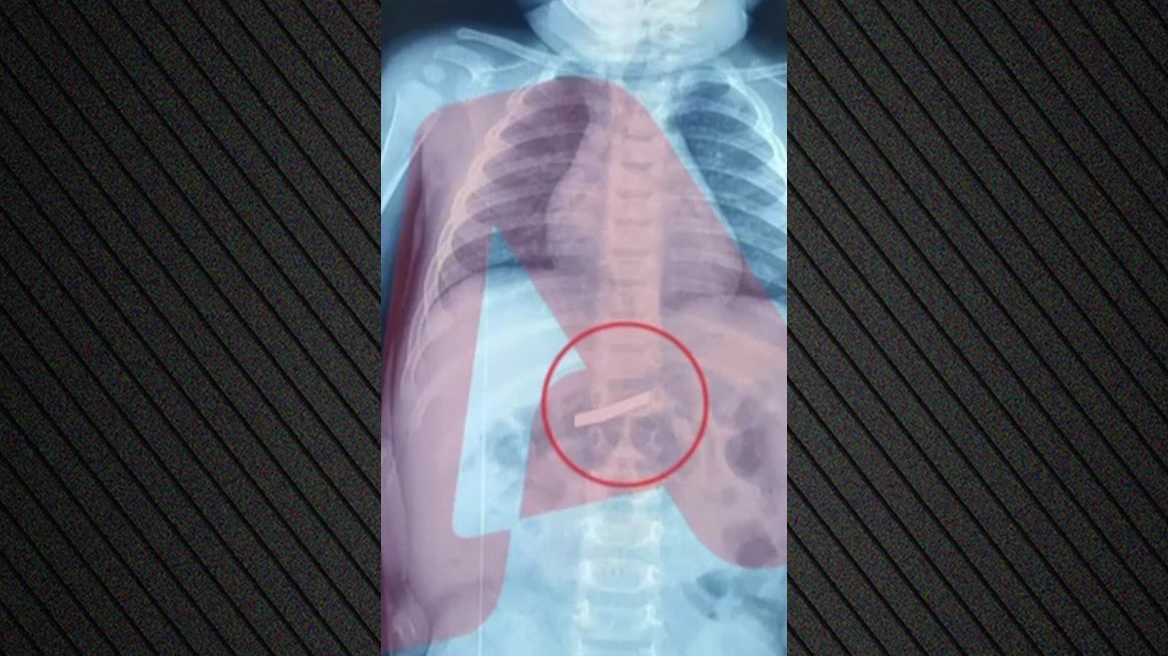

Απίστευτο περιστατικό στο νοσοκομείο Παίδων της Αθήνας όπου μεταφέρθηκε 3χρονος που είχε καταπιεί ξυράφι.

Το παιδί μεταφέρθηκε στο νοσοκομείο το πρωί της Τετάρτης (18/3) με τους γονείς να ενημερώνουν πως είχε καταπιεί ξυράφι.

Έγινε άμεσα ακτινογραφία προκειμένου να εντοπιστεί το ακριβές σημείο στο οποίο ήταν το αιχμηρό αντικείμενο, σύμφωνα με τον Alpha.

Ο 3χρονος χειρουργήθηκε και πλέον έχει διαφύγει τον κίνδυνο.